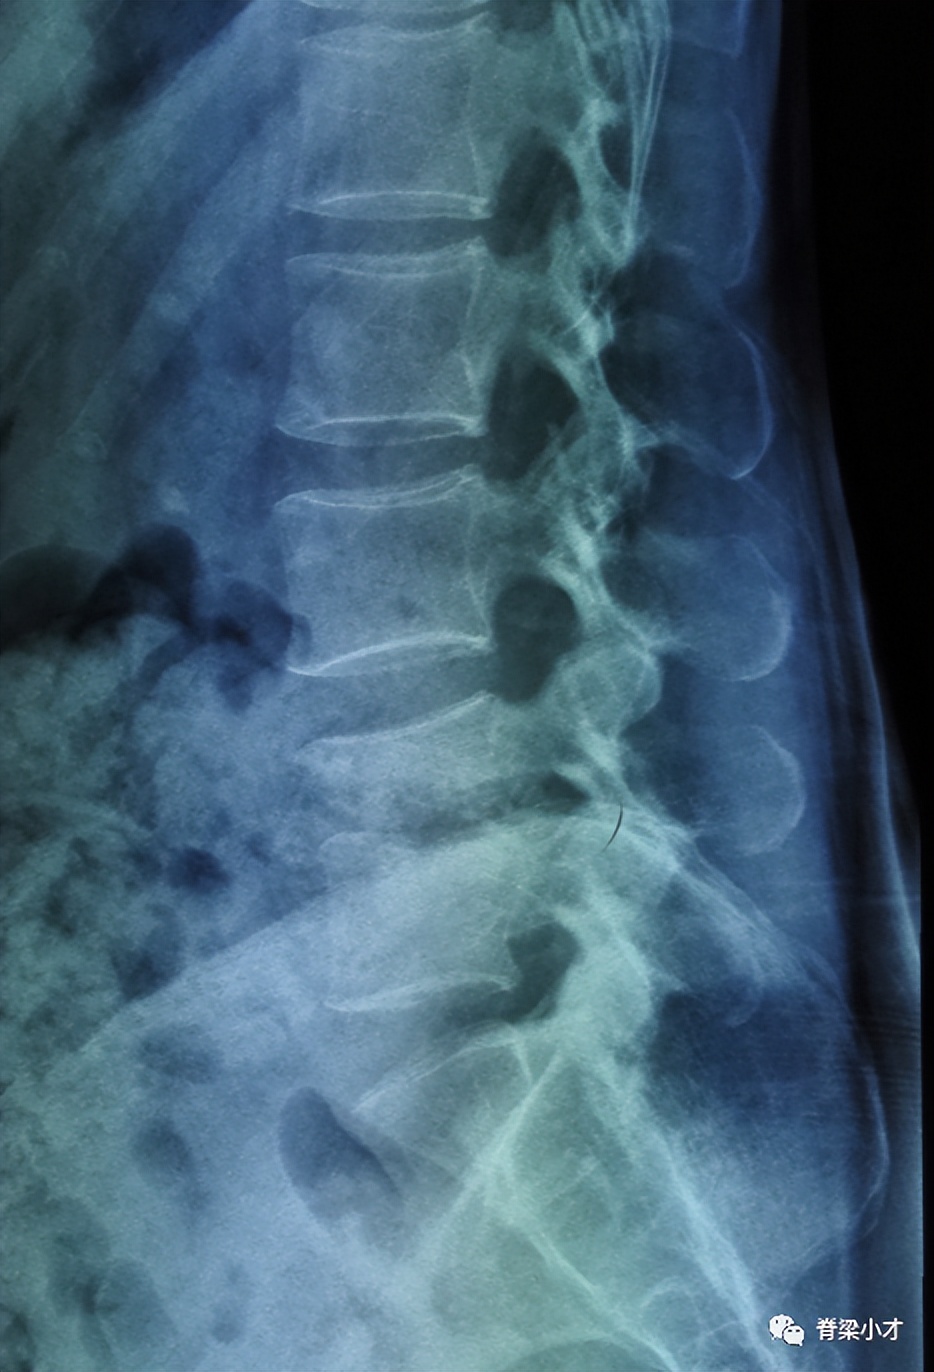

•腰椎休门病

休门病(Scheuermann’s disease)是青少年脊柱后凸的最常见病因,本病有家族性发病倾向,其遗传方式尚不明确,最新研究与COL9A3基因突变有关。近百年来人们对休门病的认识不断深入,但仍有不少尚待明确的问题。文献报告的患病率在1~8%不等,10~11岁之前几乎不会发现,12~13岁后可出现影像学改变。

腰背疼痛是最主要的症状,一般成年后可缓解。诊断主要通过医生查体并最终经X线检查确诊,典型诊断标准是在X片上连续3个椎体大于5°的楔形变,常存在许莫结节、终板不规则、椎间隙狭窄、椎体前后缘骨骺离断、椎间盘退变等。非典型休门病”的诊断存在争议;Blumenthal诊断标准:CT检查椎间隙狭窄、许莫结节和终板不规则3项中2项或核磁显示椎间隙狭窄、许莫结节、终板不规则、椎体楔形变和椎间盘信号减低5项中的3项即可诊断。有人将腰椎有此改变的称之为“腰椎休门病”。腰椎间盘突出症与腰椎休门病关系密切,腰椎休门病可能参与了腰椎间盘突出症的发病。